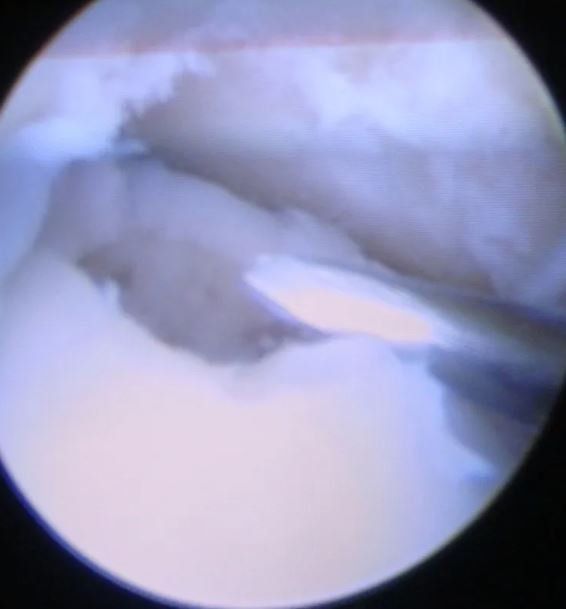

Corpi mobili intrarticolari

Cartilagine, ossa e tessuto cicatriziale possono diventare liberi e fluttuare nell’articolazione e formare quello che viene definito come corpo mobile intrarticolare. I corpi mobili possono essere dolorosi e possono causare problemi come blocchi e scricchiolii. L’artroscopia della caviglia può essere utilizzata per trovare e rimuovere i corpi mobili.